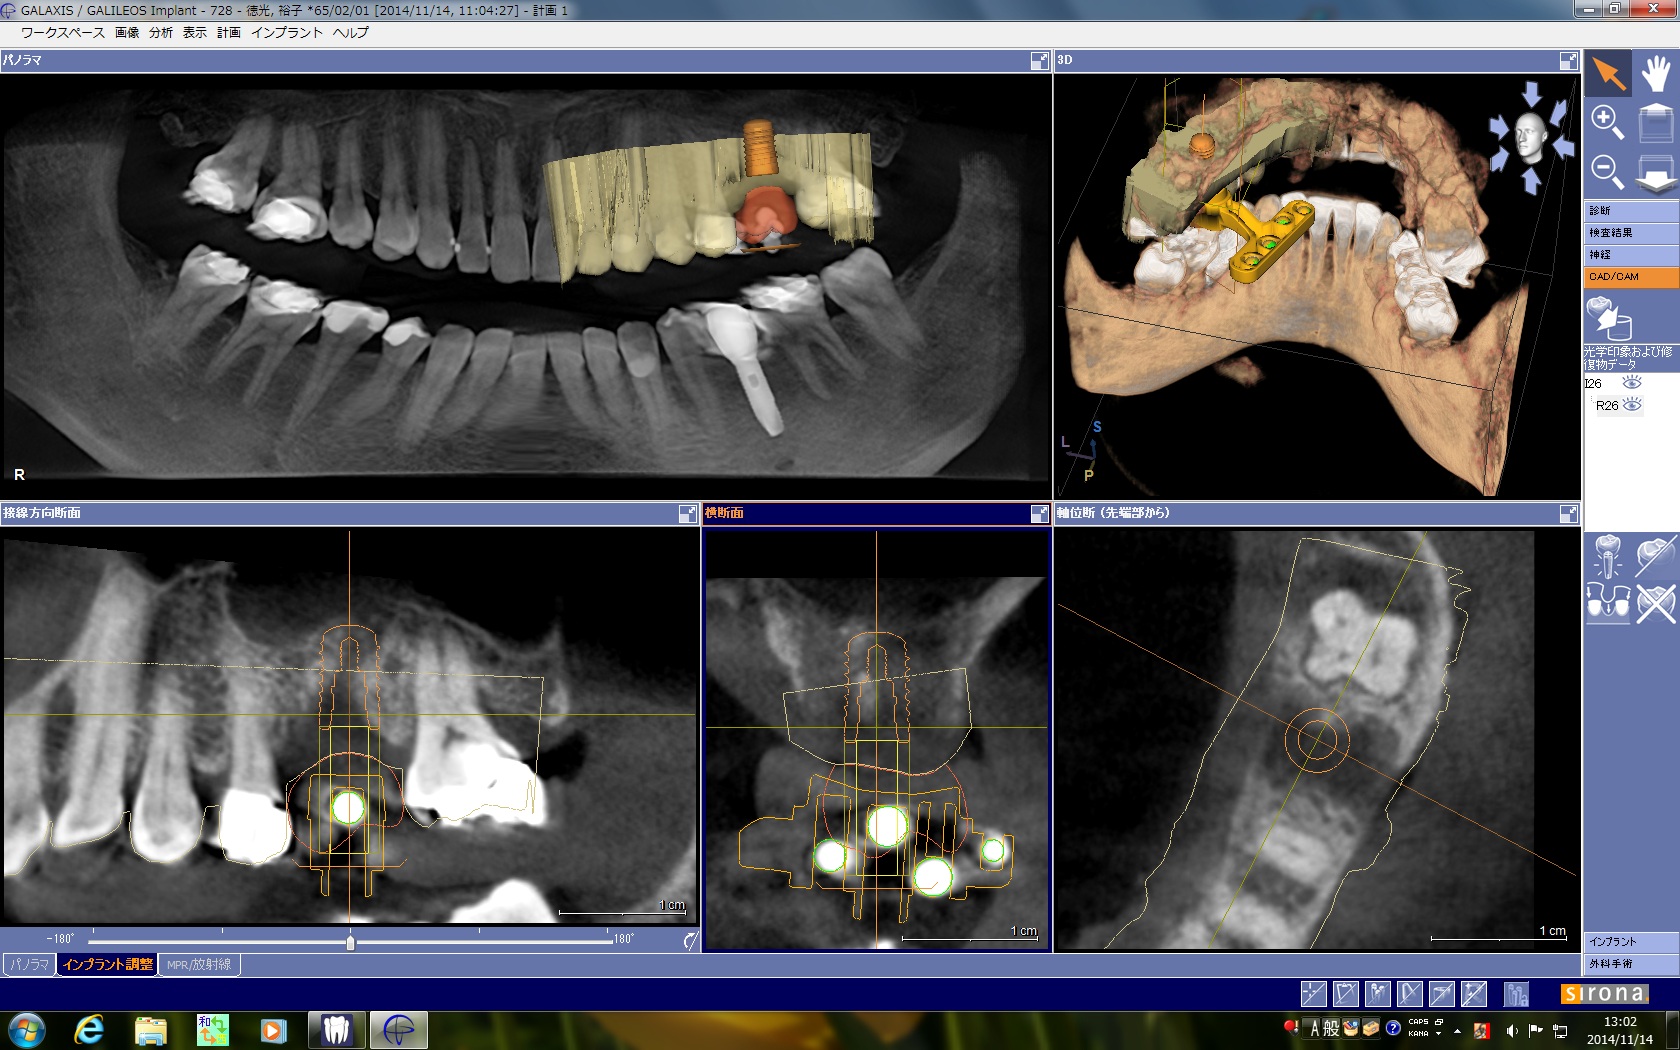

リファレンスガイドを患者様の歯に取り付けた状態でCTを撮影し、CTの画面上でインプラントの埋入位置をプランニングします。

サージカルガイドを用いてインプラント手術を行うと、治療前にCT画面で計画した通りのポジションにインプラントを入れることができます。